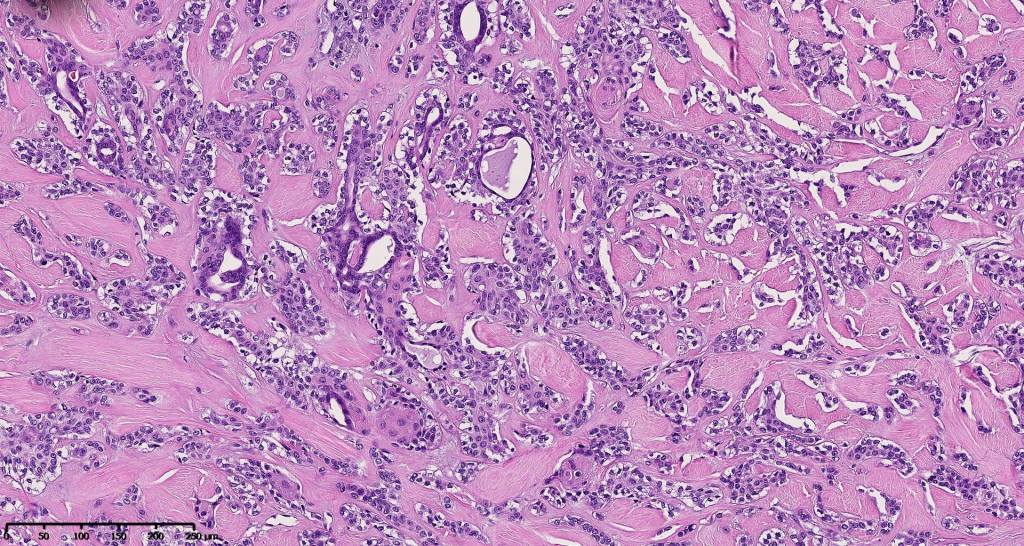

•Well circumscribed unencapsulated, nodular/multinodular silhouette composed of an admixture of epithelial & mesenchymal elements

•Mixed epithelial component including nests & cords of epithelium with abundant, eosinophilic cytoplasm & small vesicular nuclei

•Glandular differentiation sometimes showing apocrine differentiation

•Ductal differentiation

•Myxoid change

•So-called eccrine variant characterized by a pure population of small ducts compressed by dense collagen